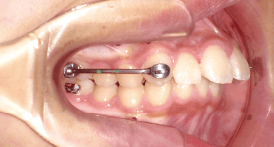

After Motion 3D Appliance - カリエールモーション装着 -

上顎の犬歯と第一大臼歯に、カリエールモーションを接着。

下顎の第一大臼歯には、チューブを接着。

なお下顎は固定源として一塊にするため、アライナー(硬めのクリアリテーナー/スプリント用のシートで製作したマウスピースなど)を装着します。

※この時、リンガルアーチを選択する場合もあります